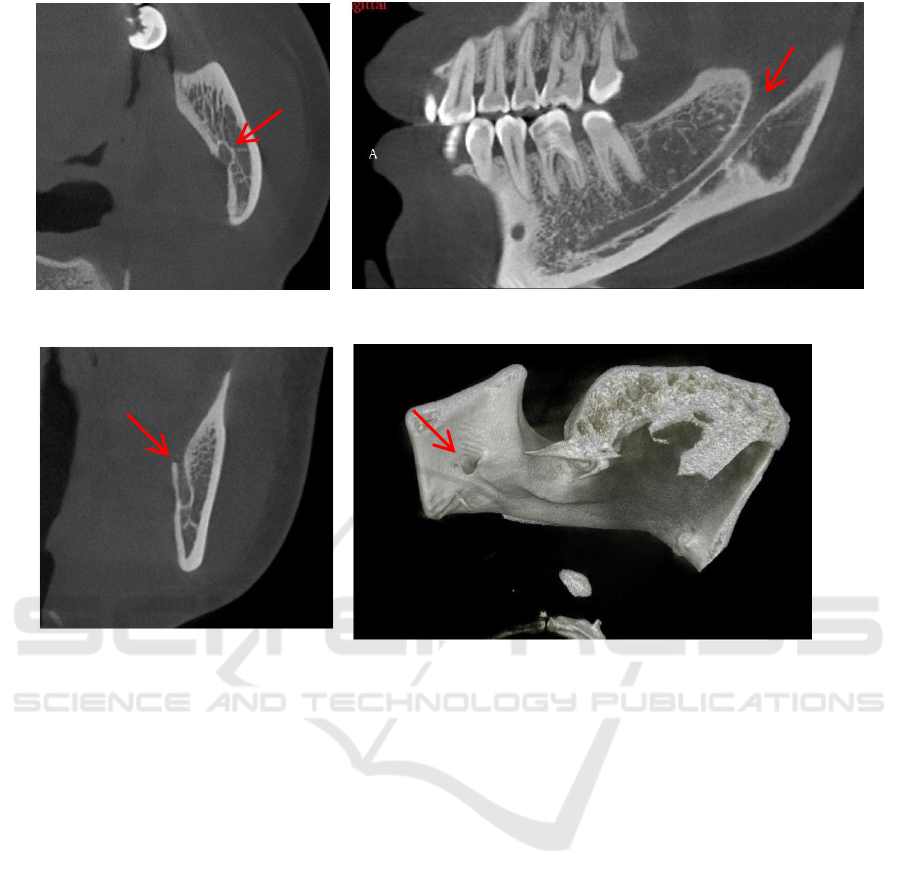

Figure 2: The posterior opening of the mandibular canal (mandibular foramen).

Axial

Sagittal

Coronal 3D view